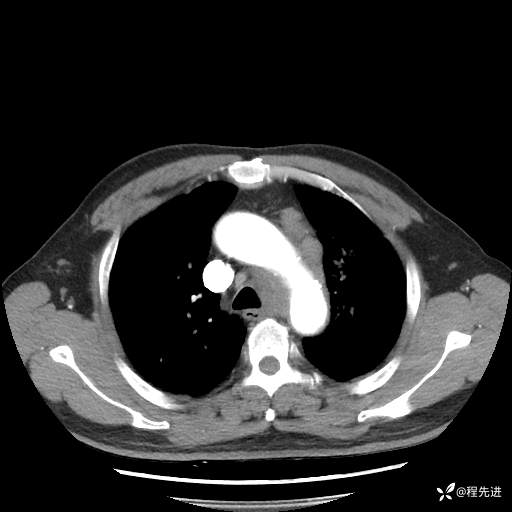

患者性别:男

患者年龄:57岁

简要病史:声嘶2月余

CT平扫+增强: